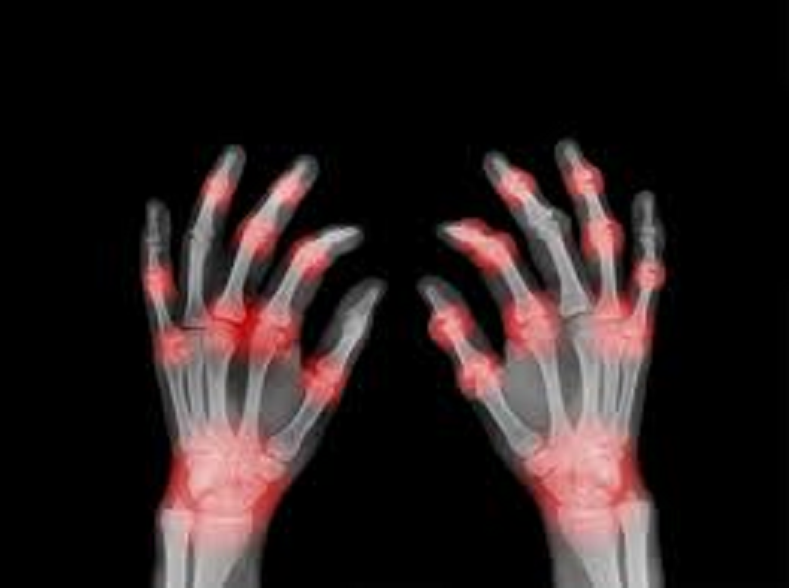

- Pain in bones and joints: You start experiencing pain in the joints of the body. It seems as if there is a lot of pain in the bones.